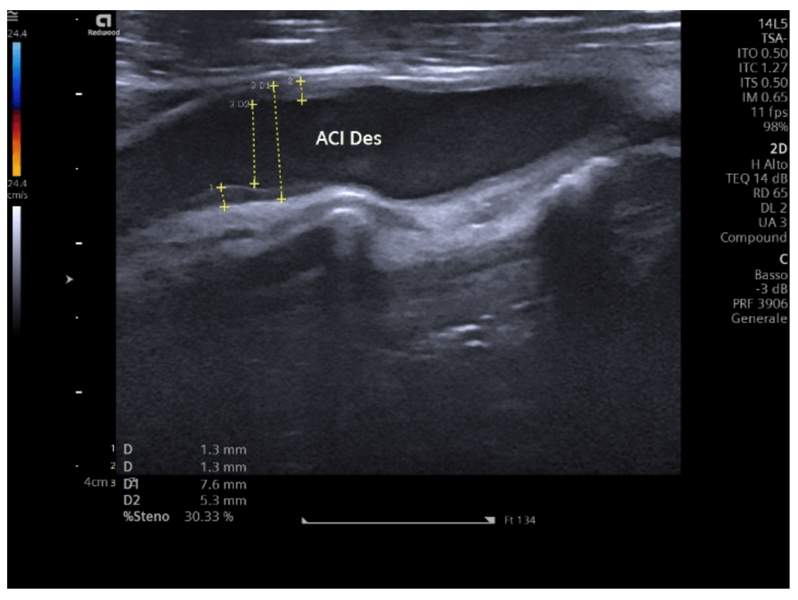

Ecodoppler dei tronchi sovraaortici

L’ecocolordoppler dei tronchi sovraortici, detto anche delle carotidi o dei vasi epiaortici...